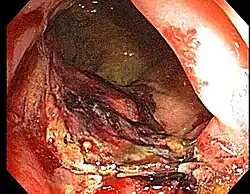

Chronic radiation proctitis

- Chronic Radiation Proctitis

- Etiology: obliterative endarteritis and chronic mucosal ischemia, leading to progressive epithelial atrophy and fibrosis. Ultimately, development of a chronically ischemic intestine prone to fibrosis and bleeding

- Symptoms: diarrhea, obstructed defecation (if strictures), bleeding, rectal pain, rectal urgency, and fecal incontinence. Rarely fistulas, SBO

- Diagnosis: colonoscopy, barium studies if suspecting strictures and fistulas

- Endoscopy (Argon plasma coagulation) - benefit for bleeding